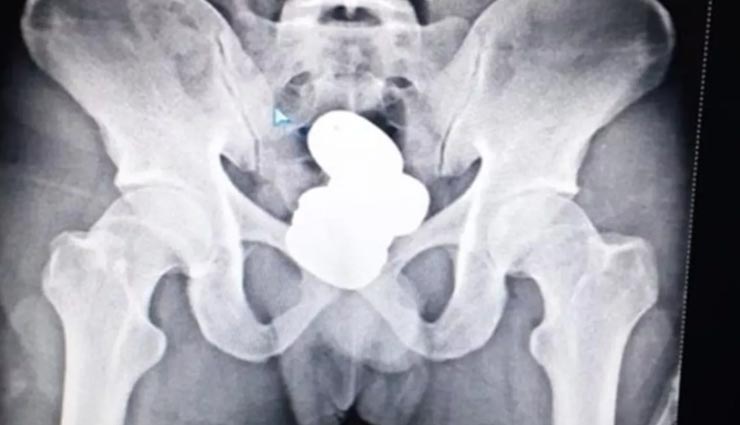

एयरपोर्ट सिक्योरिटी को उसकी हरकतों के कारण उसपर शक हुआ था। फिर उसे जांच के लिए ले जाया गया, वो काफी डरा हुआ भी था। उसके पास जो सामान था, उसमें तो कुछ नहीं मिला था। जब उसका एक्सरे करवाया गया, तो सारी बात सामने आई। एक्सरे में जांचकर्ताओं ने जो दिखा वो शॉक्ड करने वाला था। उसने मलाशय में करीब नौ सौ आठ ग्राम सोना डाला था। जिसकी कीमत करीब 42 लाख रुपये बताई जा रही है। उसने इसका पेस्ट बनाकर फिर उसे चार हिस्से में बांटकर उसके पैकेट बनाए। इसके बाद उसने इसे मलाशय में छिपा लिया। बाद में उसने बताया कि काफी मुश्किल से उसने नीचे के रास्ते अपने मलाशय में सोने का पेस्ट डाला था।